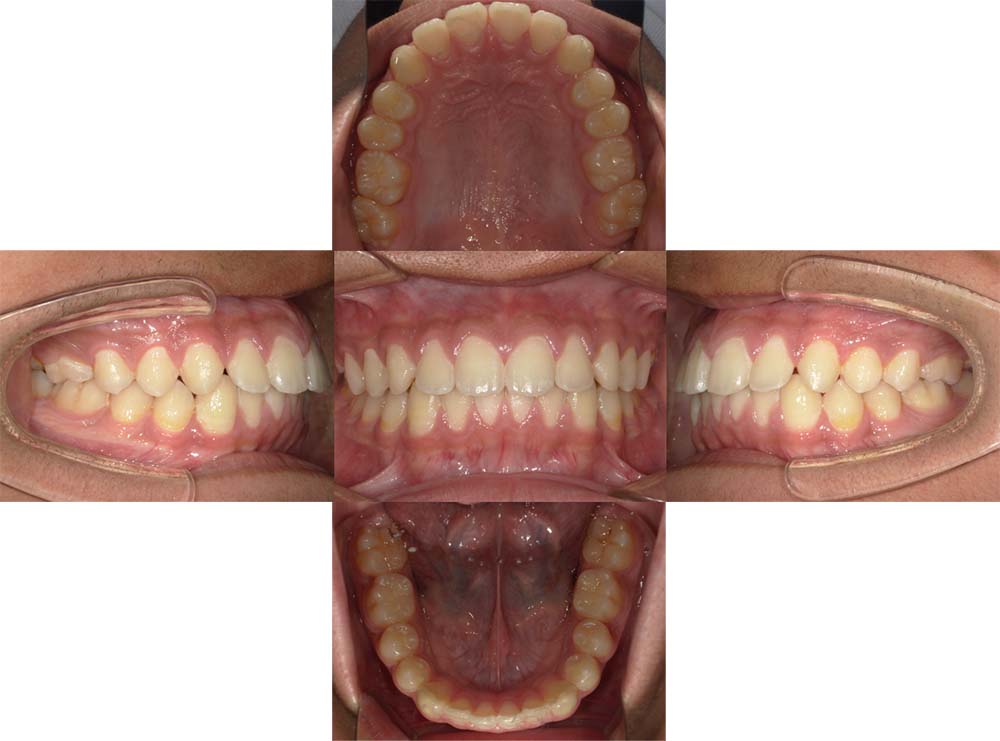

症例04

| 主訴 | 歯並びのガタガタと出っ歯が気になる。 |

| 診断名あるいは主な症状 | 上顎前突、叢生 |

| 年齢/性別 | 16歳・女性 |

| 矯正ステージ | 大人の矯正治療 |

| 治療方法 | ワイヤー矯正 |

| 抜歯部位/抜歯有無 | 抜歯 |

| 治療内容 | 抜歯したスペースを使用し、ガタガタの改善と上下顎前歯を後退させた。 |

| 費用 |

85万円程度(2025.10時点の料金となります。) ※矯正基本料金、審美ブラケットを含む |

| 治療期間 | 2年5ヶ月 |

| 主なリスク・副作用 | 痛み、歯根吸収、歯肉退縮、虫歯、後戻り |